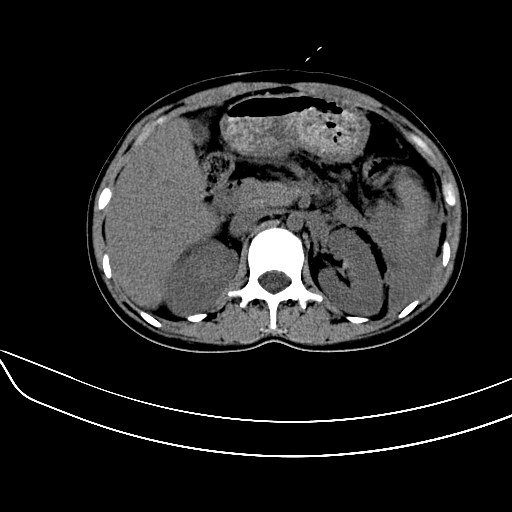

女,22岁,临床以糖尿病等病史入院,两年前有妊娠合并胰腺炎史,现有多饮、多尿、咳嗽、咳痰、左腰痛、发热等。因多种原因没做增强。

图象发的太少,第二幅图肝左内叶低密度影中似有更低密度影,建议强化.

考虑:1、不均匀性脂肪肝(肝大+不均质密度);

肝、脾增大,内见多发低密度影,少量腹水,左侧肾周筋膜增厚,结合病人糖尿病史,有左腰痛、发热,考虑:糖尿病激发肝脾病变(梗塞?),左侧肾周感染,建议进一步检查。

真可惜,这么年轻就重病缠身,患者肝内,脾,肾,左下肺,左腰大肌均见病变,结合病史考虑感染可能性大。